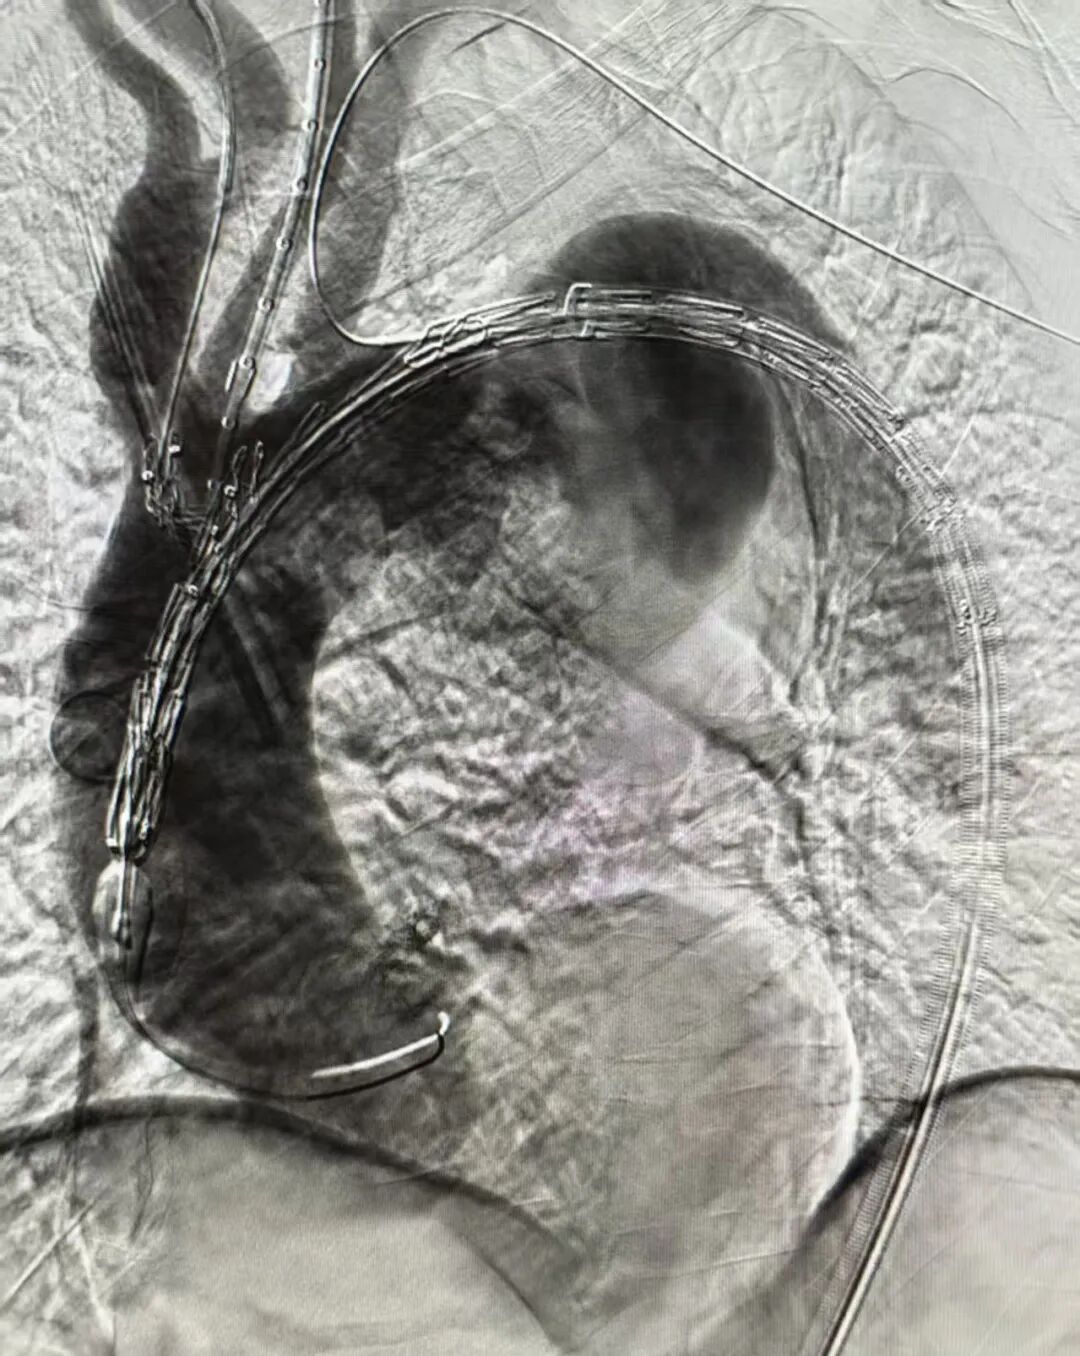

新加坡病例分享

新加坡病例手术在陈笃生医院(Tan Tock Seng Hospital)由Glenn Tan教授及其团队实施。该患者诊断为主动脉弓动脉瘤,瘤体累及左锁骨下动脉,直径达6.7cm,常规腔内手术均无法安全重建全部分支血供。患者血管解剖结构复杂,左椎动脉迷走,腔内治疗需同时完成弓上四分支的重建,这使得治疗难度进一步增加。医生团队在与心脉医疗?团队充分沟通后,决定采用定制化四分支Hector?/通天戟?胸主多分支支架进行治疗。通过单次腔内介入,精准通过其一体式分支支架重建了无名动脉、内嵌通道重建左颈总动脉,通过预埋导管重建迷走左锥动脉和导丝超选重建左锁骨下动脉,完成了全球首例四分支Hector?/通天戟?胸主多分支支架植入手术。手术过程顺利,术中无并发症,术后血管造影结果优异,瘤体被有效隔绝。

▲术中造影

▲术后造影